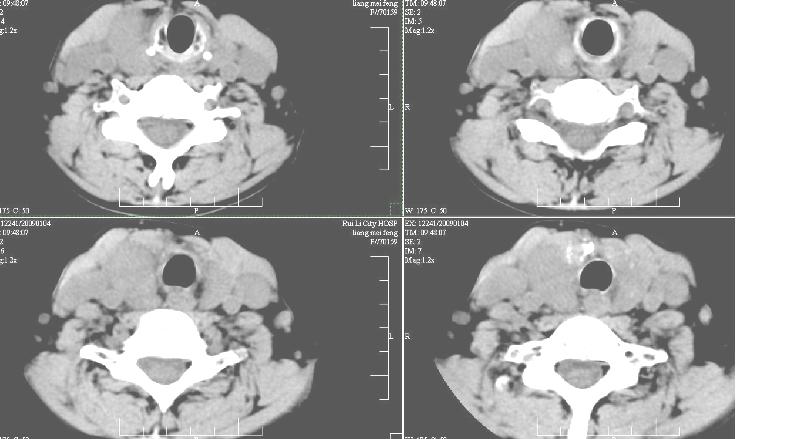

双侧甲状腺稍肿,右侧触及包块,随吞咽上下活动。 1、双侧甲状腺肿(摄碘率降低)。2、右侧甲状腺多发腺瘤,必要时增强。平扫

增强:1、双侧甲状腺肿。2、平扫甲状腺内多发占位病变,增强显示不清楚,境界欠清,请结合临床考虑甲状腺瘤。